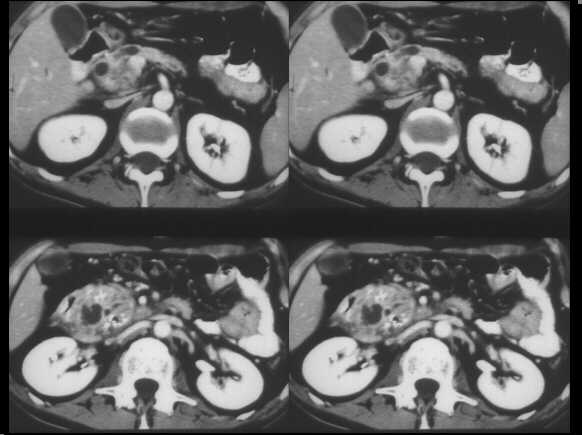

Mass-forming chronic pancreatitis. Spiral CT examination after c.m. administration. In the venous phase, the pancreatic head appears enlarged, slightly hypodense towards the remainder of the gland. A dilated MPD is recognizable within.

Cystic dystrophy of the duodenal wall – solid variant. Spiral CT examination in the venous contrastographic phase shows a thick, solid sheet-like mass between the duodenum and the pancreatic head. The fibrotic tissue is clearly hypodense in comparison to the pancreatic parenchyma.

Focal autoimmune pancreatitis of the head. Spiral CT examination, before and after c.m. administration, demonstrates an enlarged head, which appears hypodense in the arterial contrastographic phase towards the spleen. Hypodensity remains appreciable in the venous phase.